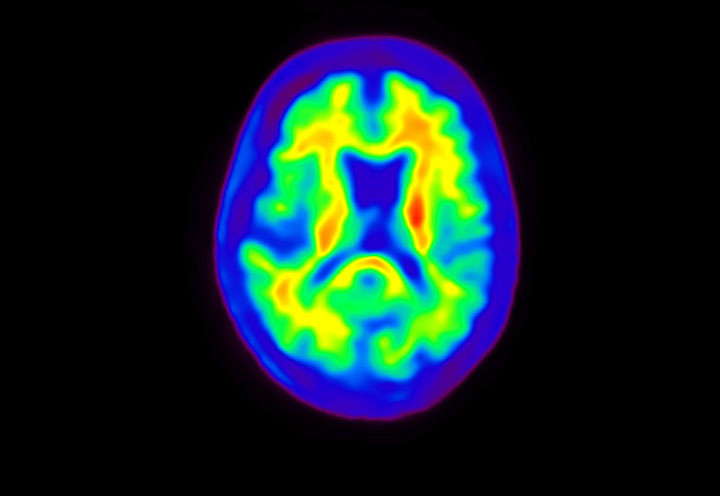

Head / Case4 : Amyloid

Axial

Courtesy : Kindai University Hospital

- Imaging protocol

- Injected dose: 3.21 MBq/kg, 18F-Flutemetamol

- Uptake time: 100 minutes

- Scan time: 20 minutes